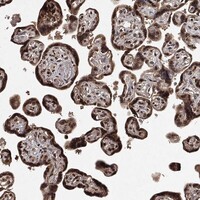

Enhanced - Orthogonal

Antibody staining mainly consistent with RNA expression data across 44 tissues.

HIGH EXPRESSION

Placenta

RNA expression: 63.5 nTPM

LOW EXPRESSION

Tonsil

RNA expression: 8.1 nTPM